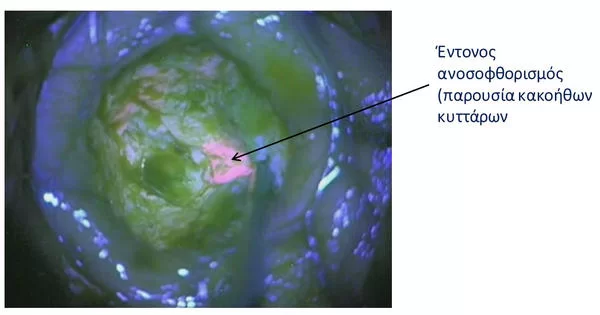

Ο νευροχειρουργός μπορεί να καθοδηγείται από μαγνητική τομογραφία στο χειρουργείο (“διεγχειρητική μαγνητική τομογραφία”) ή από μια ειδική βαφή που βοηθά στην εξέταση του όγκου υπό το μικροσκόπιο κατά τη διάρκεια της χειρουργικής επέμβασης (τεχνική 5-ALA, εικόνα 1). Μερικές φορές ο νευροχειρουργός μπορεί να συστήσει μια “λειτουργική” MRI εγκεφάλου (functional MRI) πριν από την επέμβαση, προκειμένω να καταλάβει καλύτερα που βρίσκονται οι διαφορετικές νευρολογικές λειτουργίες (ομιλία, κίνηση) στον εγκέφαλό (εικονα 2).